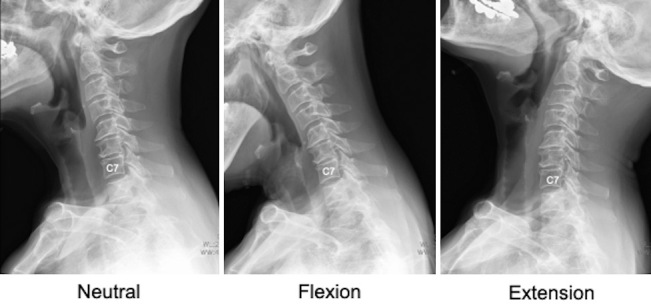

Methods: This study was a retrospective cohort analysis involving 60 patients diagnosed with cervical spine conditions and evaluated via radiographic imaging. The patients were categorized into two groups based on whether the T1 slope was clearly visible or not. Key radiographic measurements, such as the C2-C7 sagittal vertical axis (SVA) and C2-C7 Cobb angles in the neutral, flexion, and extension postures, were recorded and statistically analyzed.

Results: Significant differences were observed in the C2-C7 SVA between the groups, particularly among men. Men in the invisible T1 slope group had an average SVA of 28.9 mm, whereas those in the visible group had a mean SVA of 16.0 mm (P<0.05). Although no notable differences were observed in the Cobb angles for the neutral and flexion positions, a substantial reduction in the extension Cobb angle was noted in the invisible than in the visible group (24.4° vs. 37.6°, P<0.05).

Abstract Image